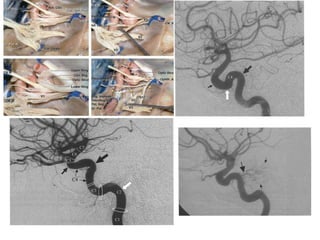

Segmentação da ACM

• M1 (esfenoidal): inicia na origem da ACM e termina em

uma curva de 90 graus (joelho), na junção dos

compartimentos esfenoidal e operculoinsular. É

subdivido em seguimento pré-bifurcação e pós-

bifurcação (proximal ao joelho).

• M2 (insular): começa no joelho, onde a ACM passa

sobre o límen da ínsula e termina no sulco circular da

ínsula, a maior ramificação acontece distalmente ao

joelho, terminam no topo do sulco circular, consistindo

em 6 a 8 artérias tronco principais.

• M3 (opercular): começa no sulco circular da ínsula e

termina na superfície do sulco lateral, estão

intimamente relacionados a superfície dos opérculos

frontoparietal e temporal. Se curvão 180 graus

formando alças.

• M4 (cortical): composto por ramos que se dirigem para

a convexidade lateral. M1 se bifurca em 6 a 8 artérias

tronco principais por hemisférios, cada tronco individual

(segmento M2 ou M3) origina tipicamente de um a

cinco ramos corticais (M4), divididos em grupos

anterior, intermediário e posterior.

As setas indicam M2 contornando o

sulco circular da ínsula. A seta maior o

ponto silviano posterior, emergência da

artéria angular.